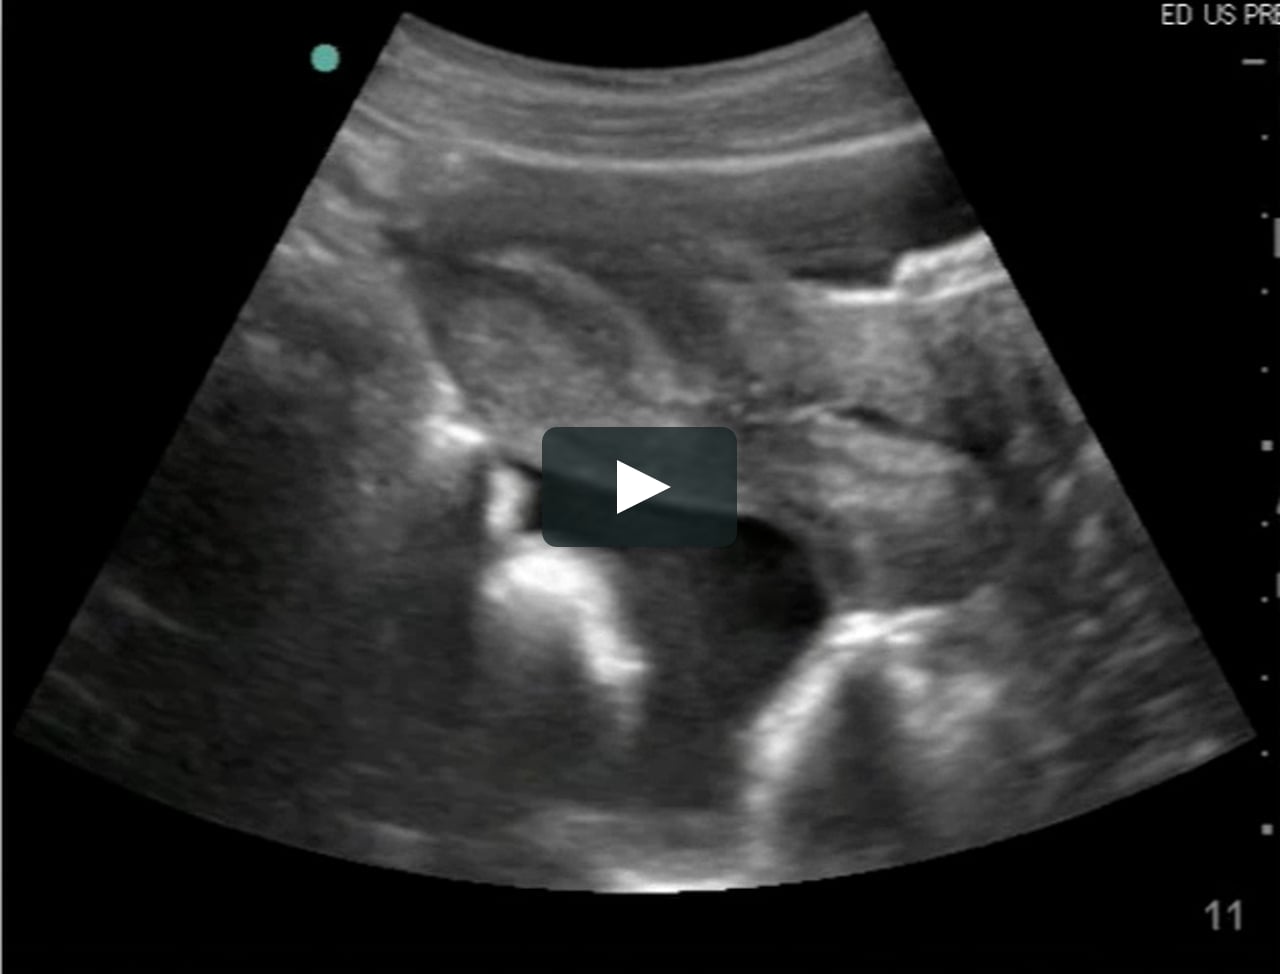

Fluid substance begins to discharge into the pouch of Douglas rapidly

FAST Video 20 Moderate fluid in pouch of Douglas on Vimeo Is Fluid In Pouch Of Douglas Dangerous free fluid in the cul de sac, a small pouch located between the back of the uterus and the rectum, can indicate. a small amount of serous fluid in the pouch of douglas is typical and helps pelvic organs move smoothly. culdocentesis is a medical procedure involving the extraction of fluid from the rectouterine pouch (pouch of. Is Fluid In Pouch Of Douglas Dangerous.